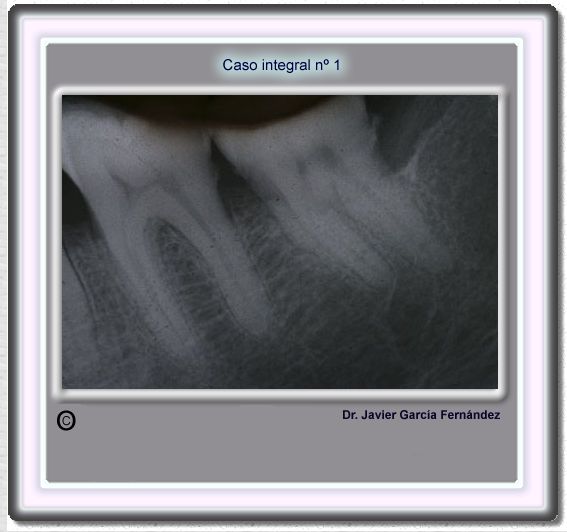

image 20